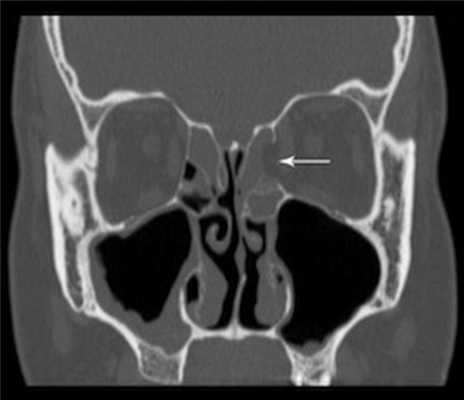

(Слева) На корональной КЛКТ в нижней части изображения визуализируется дно гипопластической ВП, находящееся выше дна носовых ямок. Утолщена слизистая оболочка обеих верхнечелюстных пазух. Решетчатые пазухи отсутствуют.

(Справа) На корональной КЛКТ определяется гипоплазия обеих ВП и аплазия левой решетчатой пазухи.